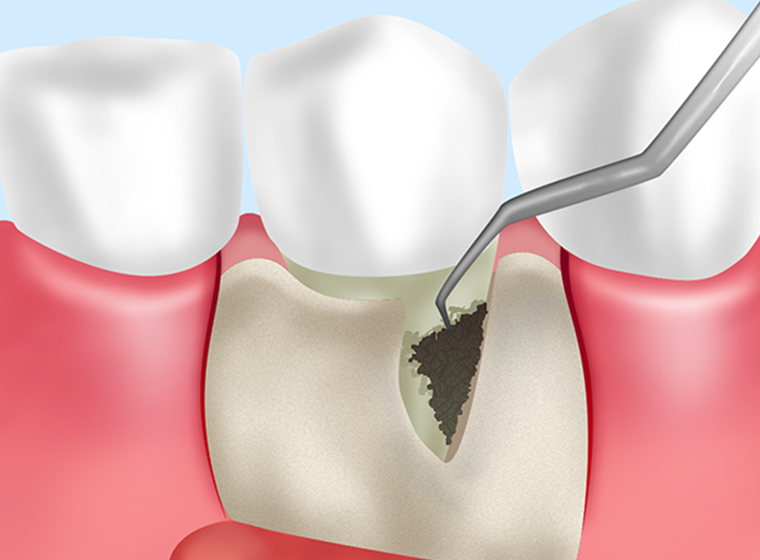

歯周ポケットそうは術

|

麻酔処置をしたあと、歯周ポケットの奥深くに付着するプラークや歯石、膿、歯周病に感染した歯肉をかき出す外科処置です。第2段階に進んでいる軽度歯周炎や中度歯周炎の治療です。 |